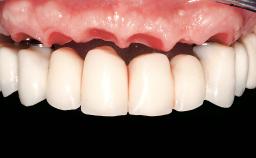

Immediate Loading of Six Implants in the Mandible and Six Implants in the Maxilla and Final Restoration with Full-Arch CAD/CAM Metal Framework FDPs Involving Digital Planning and Guided Surgery

Abutment Type CAD/CAM

Prosthesis Type FDP